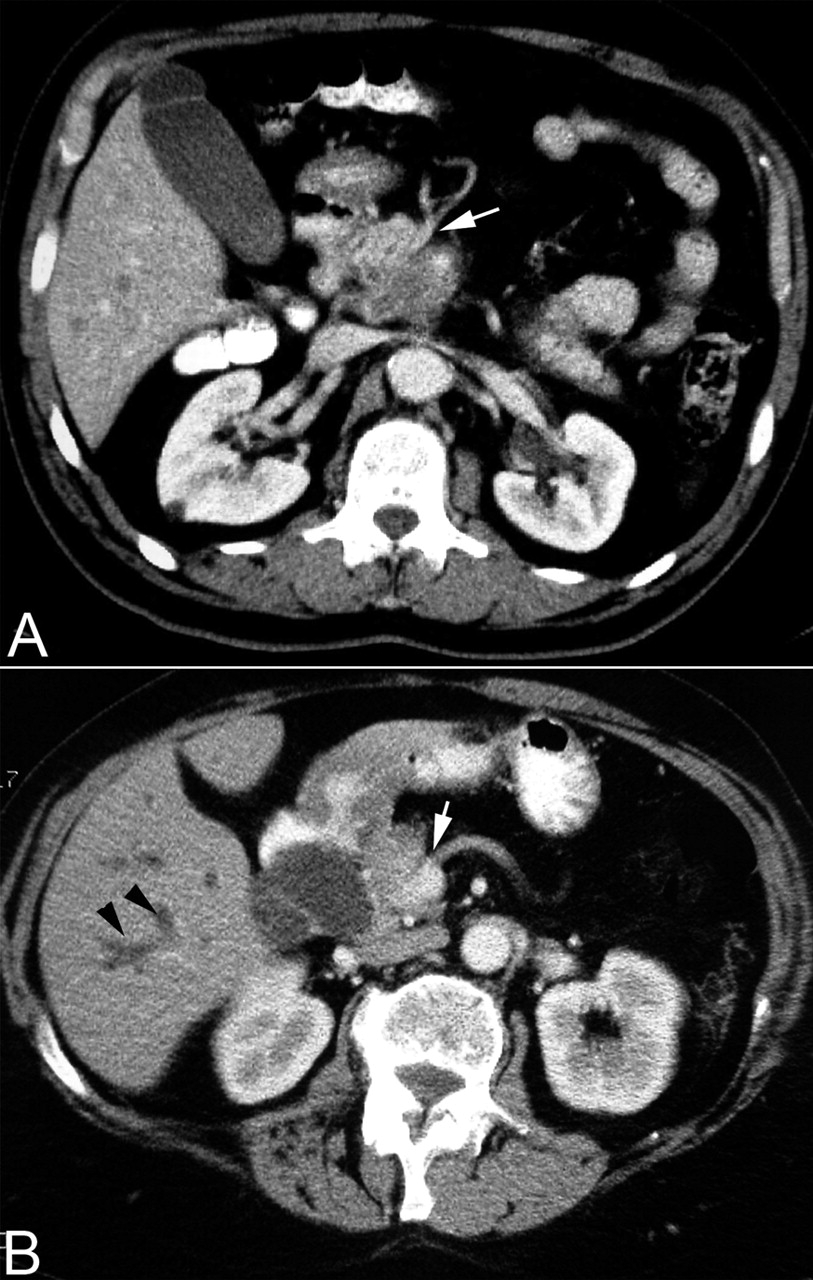

[Figure caption and citation for the preceding image starts]: Tomografia computadorizada abdominal com contraste mostrando (A) uma grande massa na cabeça do pâncreas com encarceramento da artéria mesentérica superior (seta branca) e (B) ductos intra-hepáticos dilatados (pontas de seta pretas) e encarceramento da veia mesentérica superior (seta branca)Takhar AS et al. BMJ. 2004;329:668 [Citation ends].